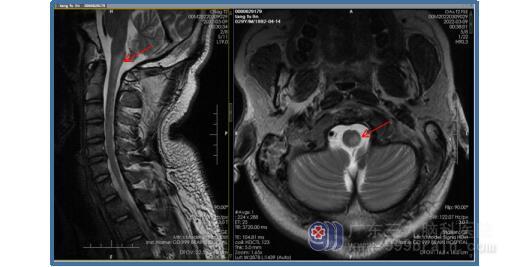

颈部MR:延髓左后下部至颈1-3水平脊髓偏左后异常信号影。

全脑血管造影术影像显示:左侧椎动脉V3段闭塞,左侧椎动脉发出脑膜后动脉后远端未见显影;右侧椎动脉经汇合部逆向代偿左侧椎动脉V4段。

根据病史、体格检查及检查结果考虑诊断为延髓左下部及颈1-3左侧急性梗塞。副院长、神经内科专家王展航针对患者病情予以改善循环、营养神经、抗血小板聚集等对症治疗,并制定了一系列康复计划。